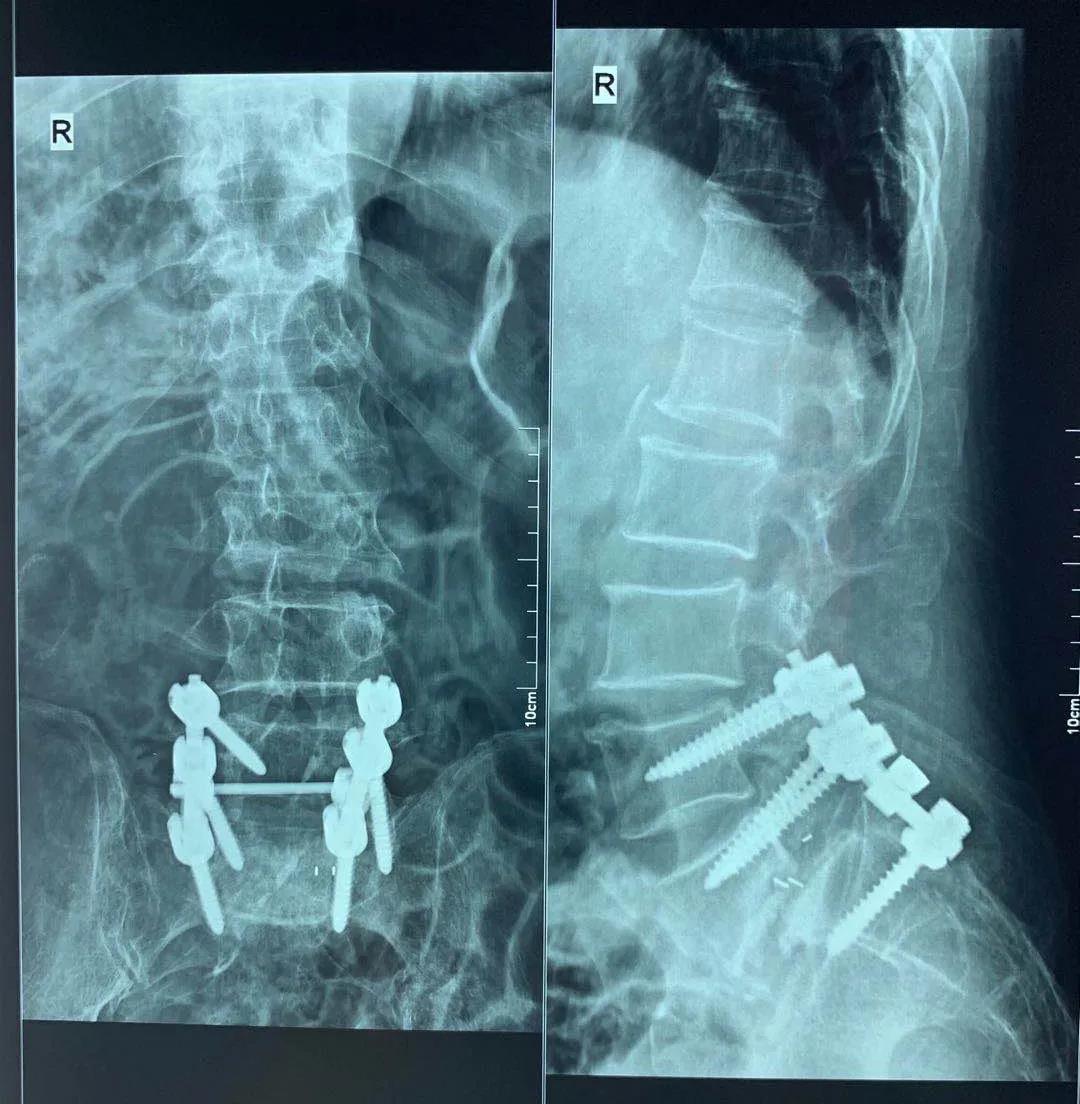

手術前

手術后